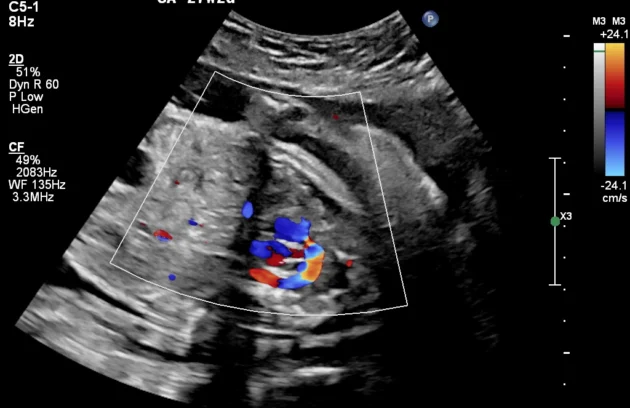

🔹 Fetal Echo / Adult Echo (Echocardiography)

Echo (Echocardiography) is a specialized ultrasound used to examine the heart. Fetal Echo evaluates the baby’s heart structure and function during pregnancy, while Adult Echo checks heart health in adults. It helps detect congenital heart defects, valve problems, and blood flow issues. If you need a fetal echo in Kathmandu, this test plays a vital role in early diagnosis and treatment planning.